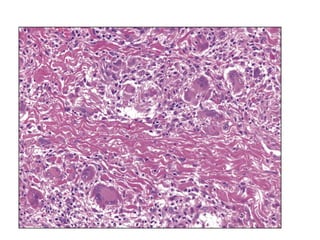

Histopatología de la micosis fungoide: infiltrado en banda subepidérmica

con epidermotropismo.

Linfocitos atípicos epidermótropos, aislados o agrupados en tecas, que predominan en la parte

inferior de la epidermis y se caracterizan por un núcleo de tamaño pequeño

a mediano, hipercromático.

La inmunohistoquímica muestra su naturaleza T linfocítica CD3(+).